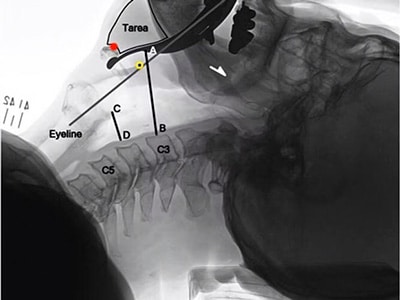

X線画像データに基づきブレードの中間湾曲を強化、より有効に舌根を制御できるようにしています。